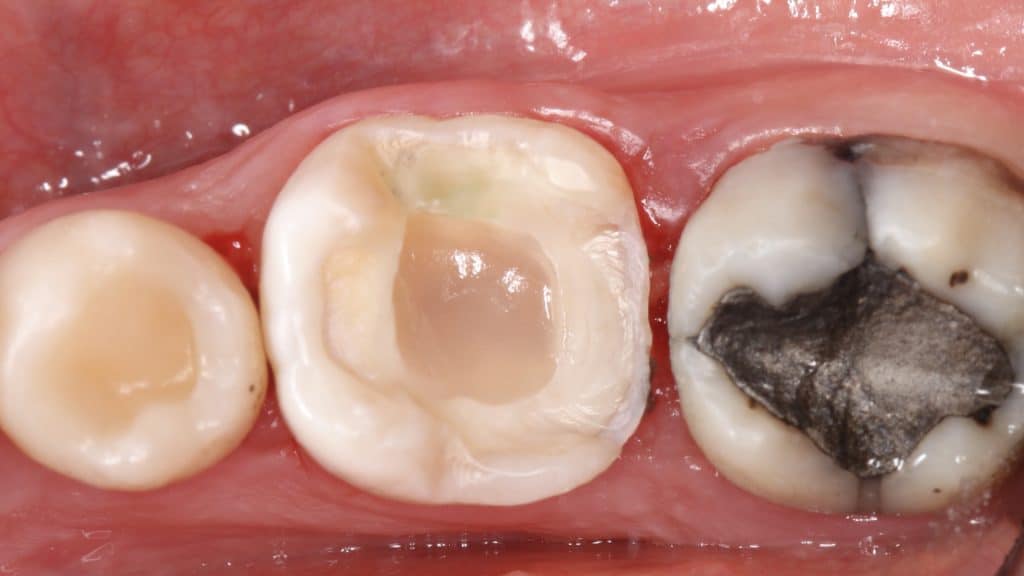

A young female patient presented to the clinic with spontaneous pain at the lower left first molar; the patient also complained about food impaction. A large carious cavity was found upon examination.

After isolation with the rubber dam, we started cleaning the cavity. Pre-wedging was used to avoid harming the proximal periodontium.

Caries reached the pulp, as you can see from the bleeding in the distal area.